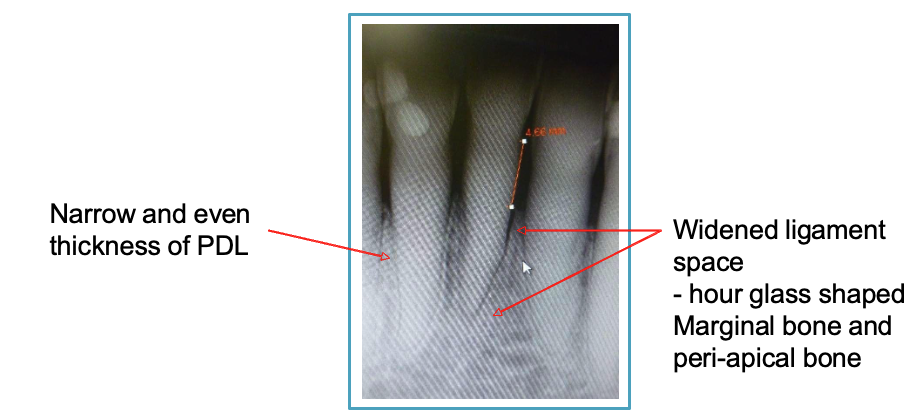

describe 2 characteristics of periodontal bone when it's adapting to strong occlusal forces

narrow + even thickness of PDL

widened PDL space: hour glass shape of marginal + peri-apical bone

4 histological signs of occlusal trauma

resorption of collagen, bone, cementum

widened PDL

increased mobility

no attachment loss

what are the numbers